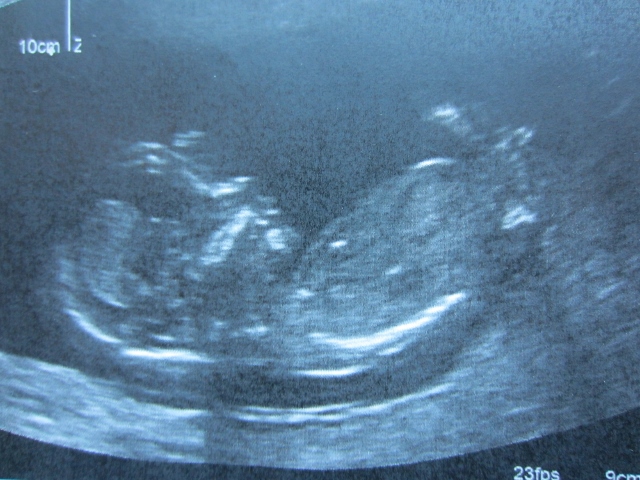

13 + 2 days

At the end of the scan, the tech only gave me about a minute to watch the babe. The nub seemed longish and flat, but it was coming in and out of focus so I couldn't study it very closely. It didn't seem like a typical girl nub with a fork - it looked like a long line with a little line on top and a little line on the bottom (which is different from this picture which shows two parallel lines). Does that sound more like a boy nub? Thanks!

Hmmmm.....I don't know. Baby is curled and I don't feel like the nub is classic boy or girl. I'm 50/50 on this one